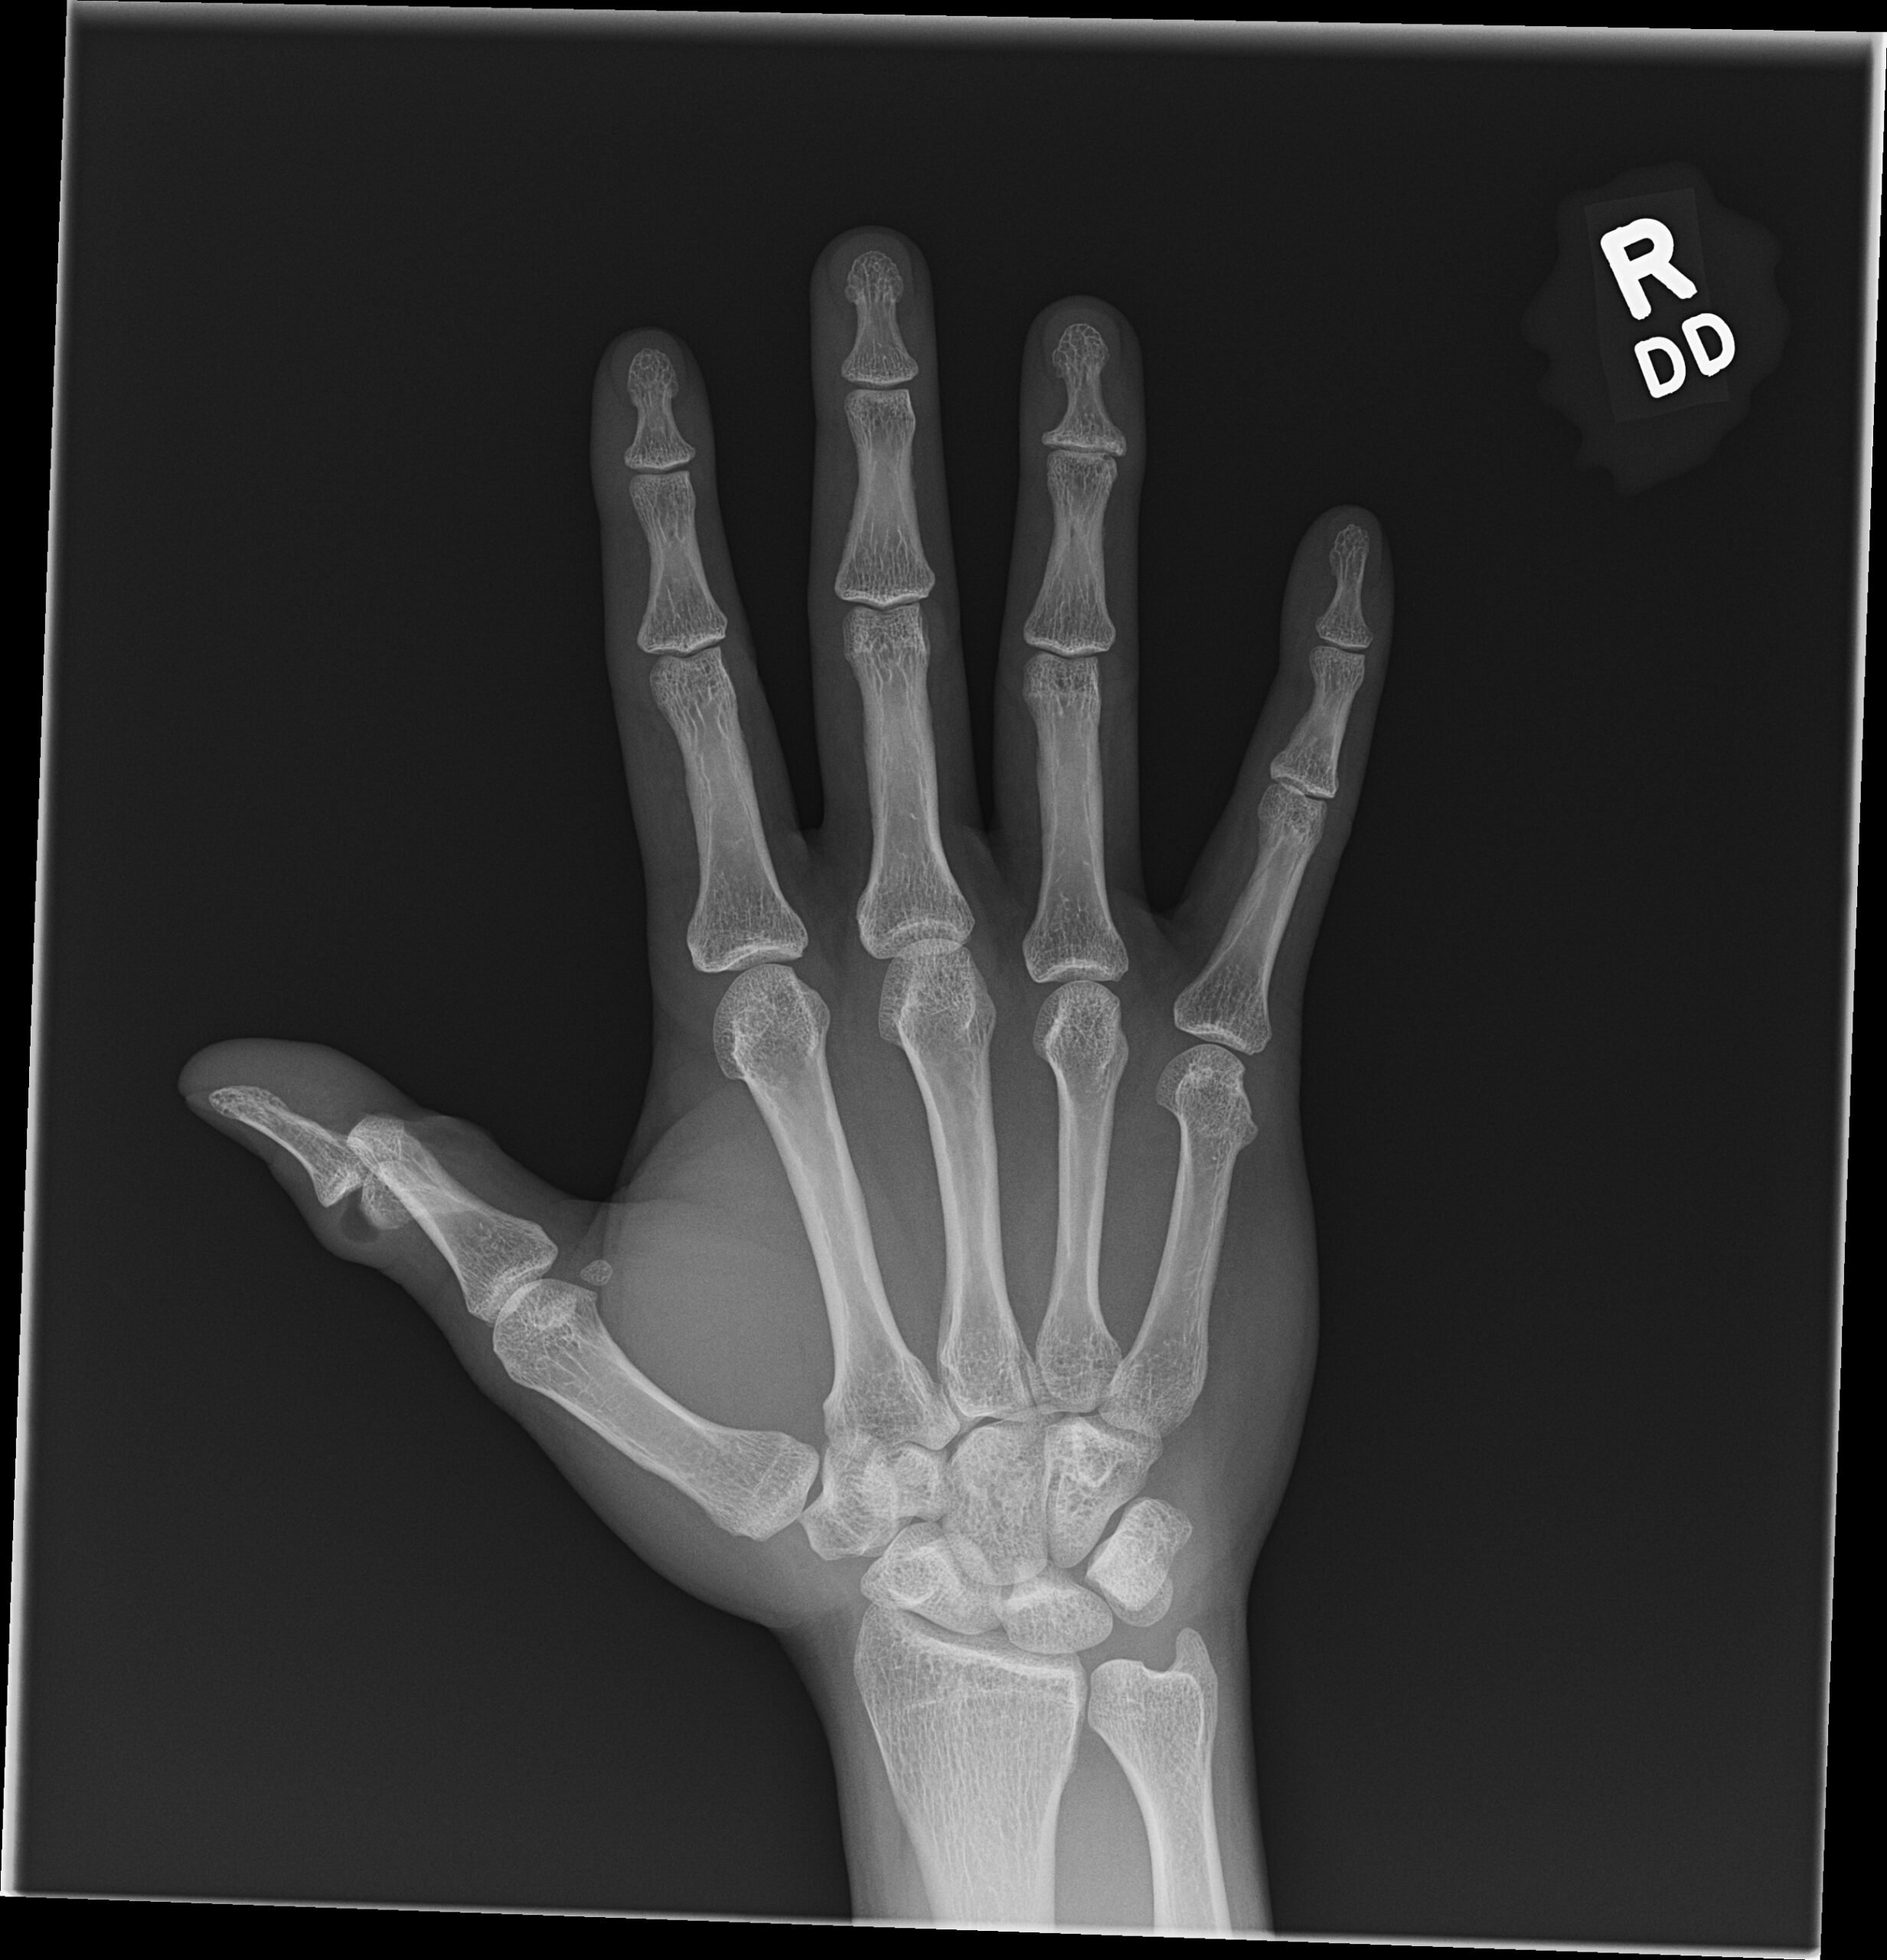

Open fractures represent high acuity injuries requiring rapid evaluation and management for optimal outcomes. In this report, we discuss a patient presenting with an open fracture of the proximal phalanx of the right thumb with interphalangeal (IP) joint dislocation. The patient reported that the injury occurred in the setting of trauma from catching a cricket ball, experiencing immediate severe pain and bleeding. Key interventions in the emergency department included rapid x-ray evaluation of the injury, administration of cefazolin and tetanus vaccine, pain control, covering the exposed bone in moist gauze, and involvement of the hand surgery team for bedside irrigation and reduction. He underwent open reduction and internal fixation of the fracture the next day. He was followed in the hand clinic and was doing well at the 12-week appointment. In summary, we report on an open fracture and dislocation of the proximal phalanx of the thumb secondary to a traumatic cricket injury. Early mobilization of the surgical team and adjunctive prophylaxis with cefazolin and updated tetanus were key measures in the emergency department for achieving optimal outcomes.